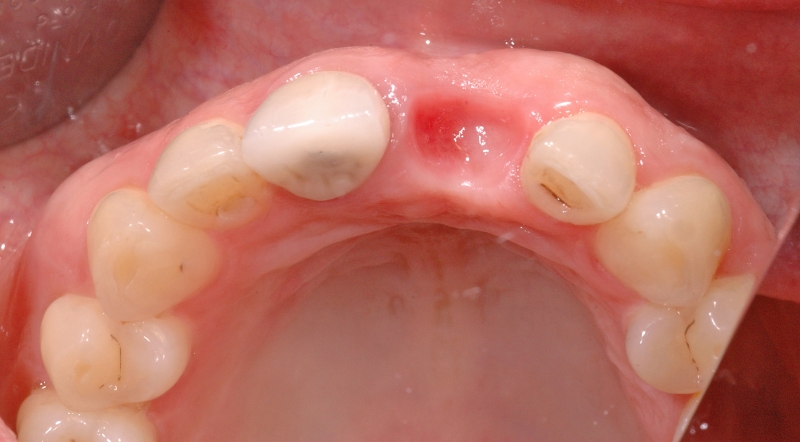

4/18 - Clinical situation, occlusal viewGBR together with soft tissue augmentation with mucoderm® and maxresorb® - Dr. S. Scherg